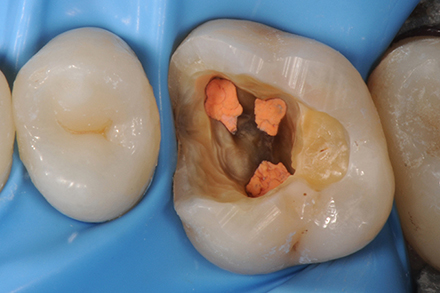

The MBII canal has been found, shaped and sealed up to the confluence with the MBI canal.